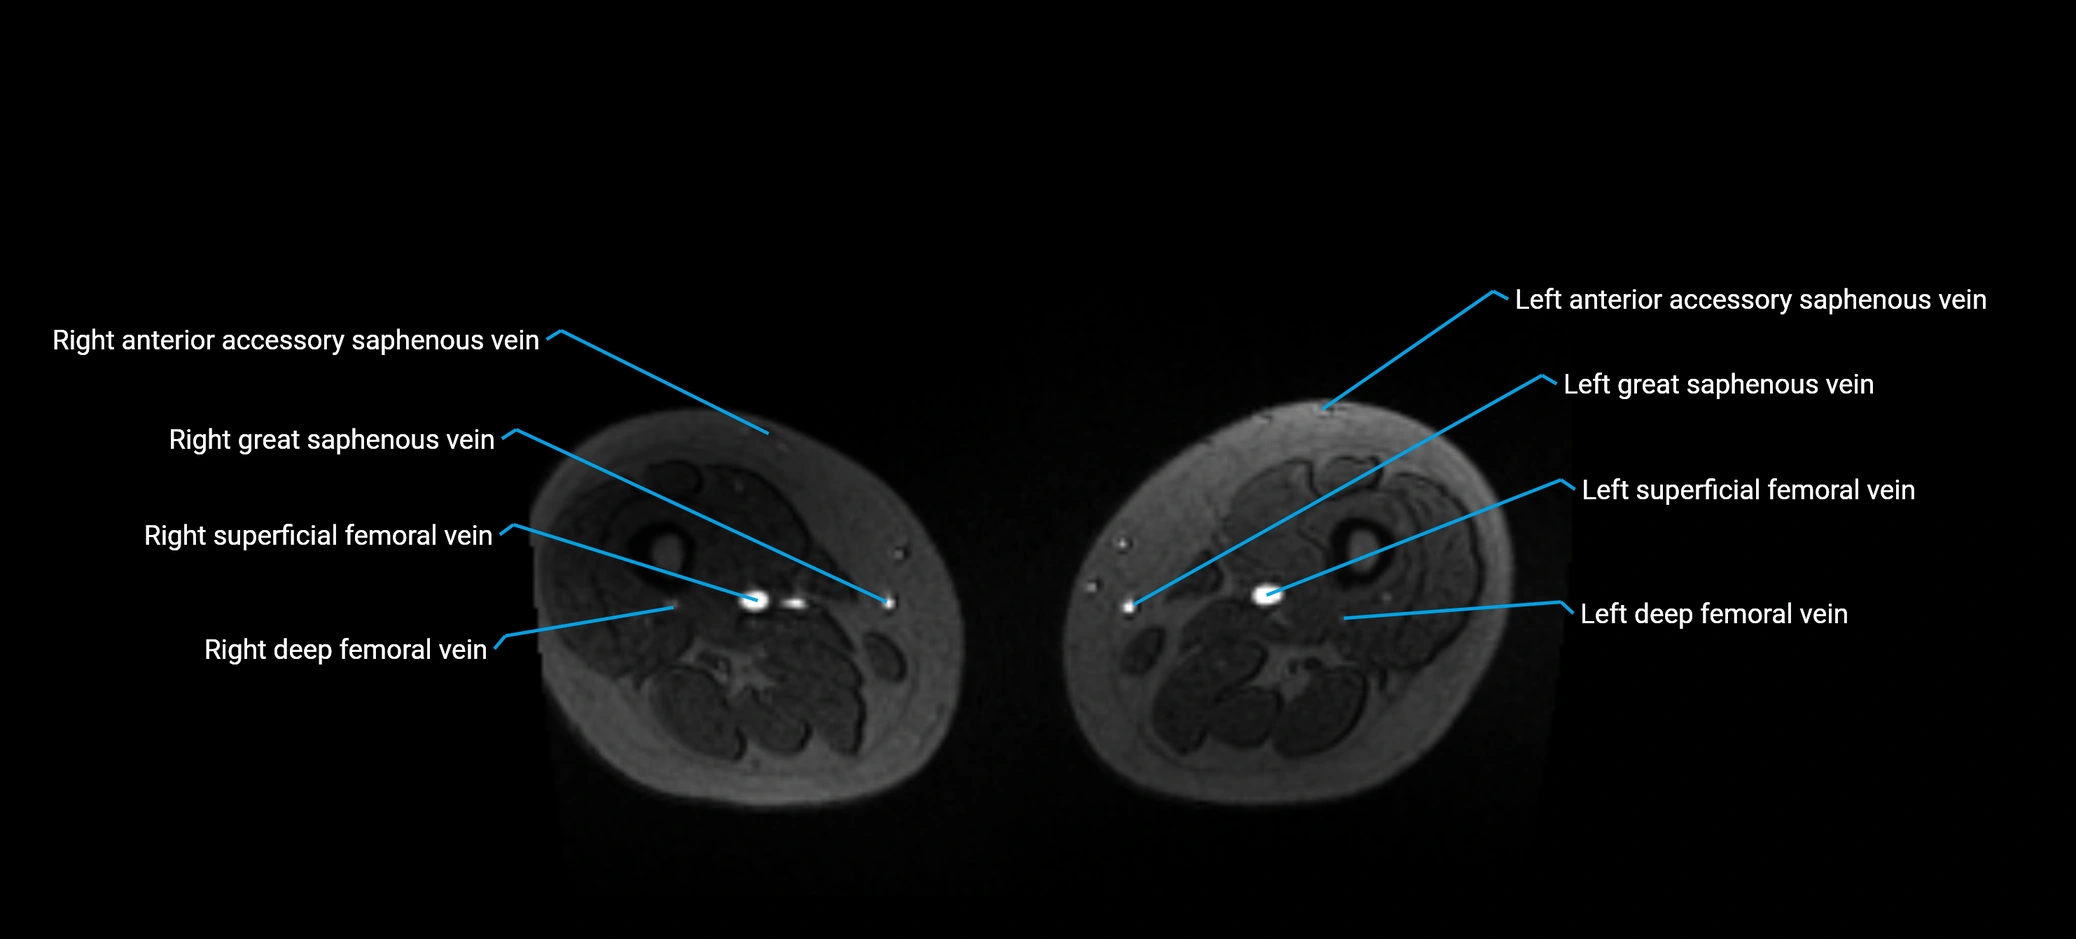

MRI image

image